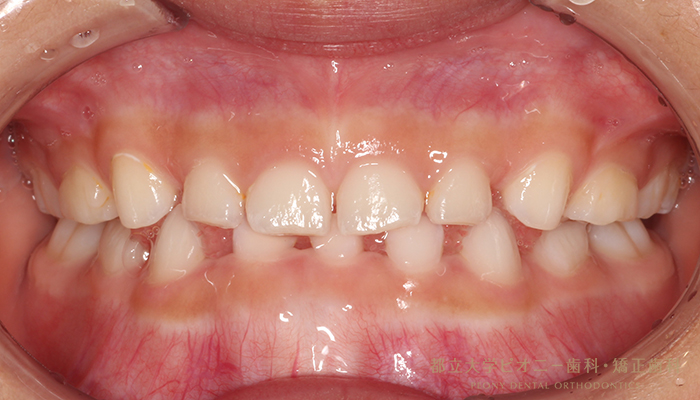

Case1

Before

After

| 主訴 | 受け口が気になる |

|---|---|

| 治療期間 | 6か月 |

| 治療費 | 88,000円(税込) |

| 治療内容 | ムーシールド(筋機能療法) |

| 治療のリスク | ・使用できる時期が限られている。 ・装置に慣れるまで時間がかかることがある。 ・鼻呼吸が難しいと使えないことがある。 |